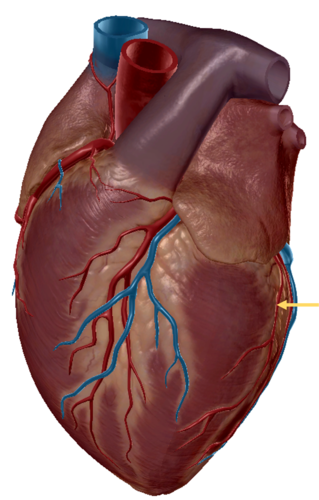

great cardiac vein

middle cardiac vein

coronary sinus

posterior interventricular sulcus

small cardiac vein